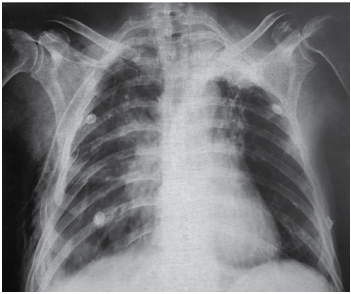

Paciente vítima de trauma moto versus auto foi diagnosticado com pneumotórax direito, e esse paciente foi drenado pelo médico que o atendeu. Ao assumir o plantão,

outro médico reavalia o paciente, que mantém queixa de

dor em hemitórax direito, taquipneia e murmúrio diminuído à direita, com saturação de 93% com 2L de oxigênio.

A radiografia realizada é a seguinte:

(Arquivo pessoal; imagem usada com autorização)

Assinale a alternativa que apresenta a conduta correta a ser empregada nesse momento.